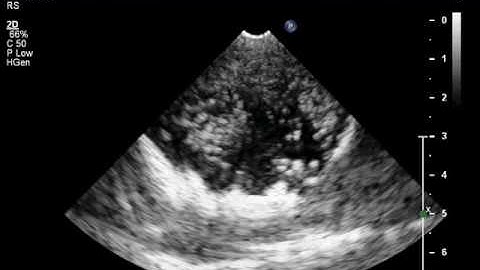

Microbubble Cavitation - Low Output Power